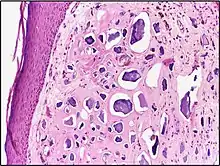

![]() | Capillary hemangioma | Micrograph showing capillary hemangioma of skin. | Category: Histopathology of capillary hemangioma | Capillary hemangioma |